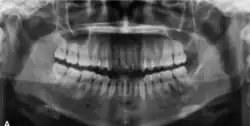

In its early stages, central ossifying fibroma (COF) appears as a small, well-defined radiolucent lesion due to its fibrous tissue content. Differential diagnoses at this stage include periapical pathology, central giant cell granuloma, and ameloblastoma.[22][23] As the lesion matures, it exhibits a mixed radiolucent-radiopaque appearance due to progressive calcification.[22] At this stage, it should be differentiated from other mixed jaw lesions such as fibrous dysplasia, calcifying epithelial odontogenic tumour, adenomatoid odontogenic tumour, and condensing osteitis.[22] In its mature form, COF may appear predominantly radiopaque, resembling lesions like odontomas, osteoblastomas, or osteosarcomas radiographically.

COF typically presents with well-defined, smooth, and often corticated borders. As a central lesion, it originates within the medullary bone and expands concentrically in all directions.[24] With growth, it may cause tooth displacement, root resorption, inferior displacement of the mandibular canal, and loss or alteration of the lamina dura of adjacent teeth.[25]

In conclusion, COF most commonly occurs in the mandible and expands from a central epicenter. Radiographically, it presents as a well-defined mixed-density lesion,[26] and Cone Beam CT (CBCT) plays a crucial role in its accurate diagnosis and assessment.

Central Ossifying Fibroma (COF) typically presents as a painless swelling in the posterior mandible, though maxillary involvement can also occur.[31] Larger lesions may lead to facial asymmetry and displacement of adjacent teeth.[32] Radiographically, COF appears as a well-circumscribed, mixed radiolucent–radiopaque lesion with a characteristic sclerotic border, and the degree of radiopacity reflects the stage of mineralization.[33] Cone-beam computed tomography (CBCT) offers detailed evaluation of cortical expansion, root displacement, and internal architecture.[34]